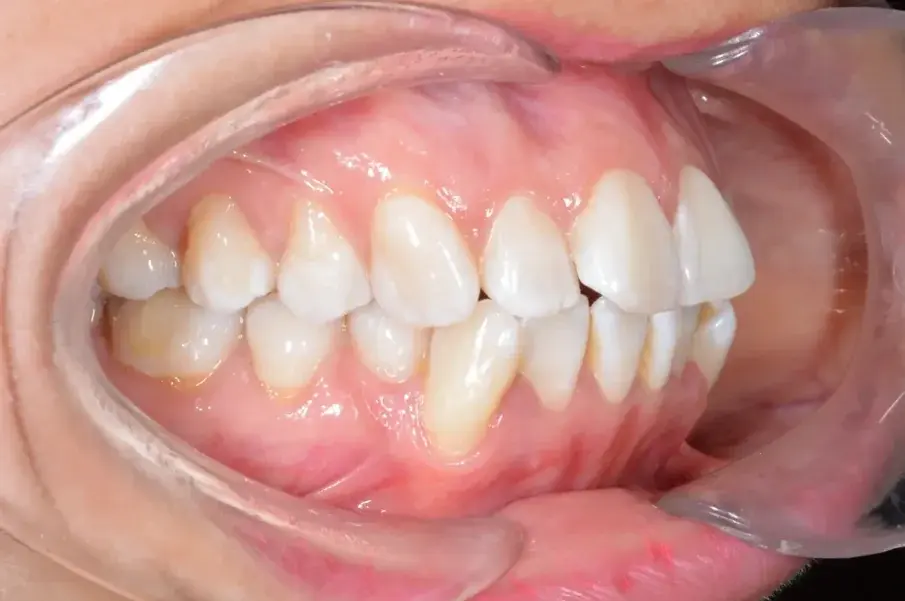

Фиг. 2а: Първоначални интраорални изображения.

Фиг. 2b: Първоначални интраорални изображения.

Фиг. 2c: Първоначални интраорални изображения.

35-годишна пациентка постъпва със струпване на зъби, болки в мускулите и ставите и главоболие след събуждане. При прегледа се установява I скелетен клас със струпване и бимаксиларна протрузия. Изследването на лицето показа конвексен профил с изпъкнали устни и квадратна форма на лицето, която се засилва при усмивка (фиг. 1-4). Тя съобщава за бруксизъм и се наблюдава двустранна хипертрофия на масетерите, но няма изменения в темпоромандибуларните стави.